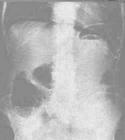

腹腔内存在游离气体的现象.多由胃肠道穿孔等所致.表现为腹部叩诊肝浊音区消失.病人站立作X线检查时,可见膈下有游离气体.如因消化性溃疡伤寒等并发急性胃或肠穿孔时,须立即手术治疗.因诊断和治疗上需要将气体注入腹腔内所致的气腹,称人工气腹.